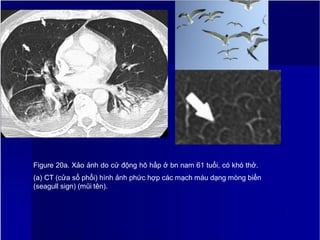

Figure 20a. Xảo ảnh do cử động hô hấp ở bn nam 61 tuổi, có khó thở.

(a) CT (cửa sổ phổi) hình ảnh phức hợp các mạch máu dạng mòng biển

(seagull sign) (mũi tên).

Figure 20b. Xảo ảnh do cử động hô hấp ở bn nam 61 tuổi, có khó thở.

(b) CT (cửa sổ trung thất) cho thất bất thường giảm đậm độ do hiệu ứng thể

tích

2

5

từng phần (mũi tên), dấu hiệu rất giống PE.